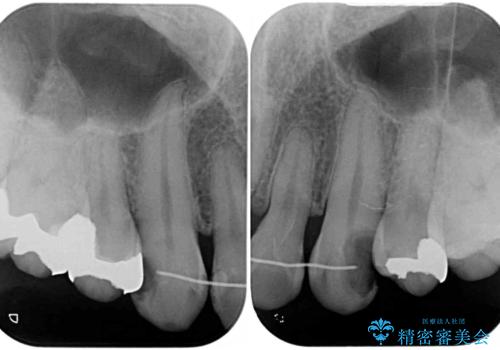

- 以前矯正を行った際に前歯が虫歯だらけとなり、審美面を気にして来院された患者様です。

虫歯の大きかった左右犬歯はオールセラミッククラウンで補綴治療をおこない、4前歯は研磨や古い充填物の詰め直しを行いました。